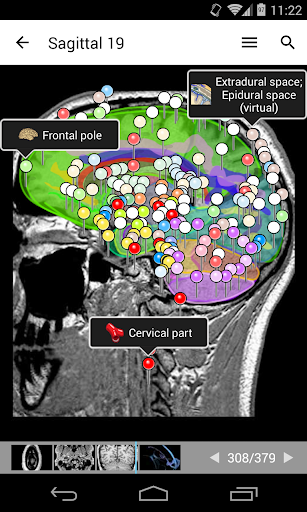

- يتميز وضع الدبابيس بسلوك جديد يسمح لك باتباع بنية تشريحية بسهولة أكبر

- يمكنك الآن تحديد حجم الخط الذي تفضله يدويًا لتسميات الهياكل التشريحية (في وضع الملصقات)

- ضمن عرض التفاصيل للبنية التشريحية ، يشير الدبوس الآن إلى البنية ذات الصلة في جميع الصور الحالية

انقر أيضًا مباشرة على الصورة للانتقال إلى الصورة المعروضة في تلك الوحدة